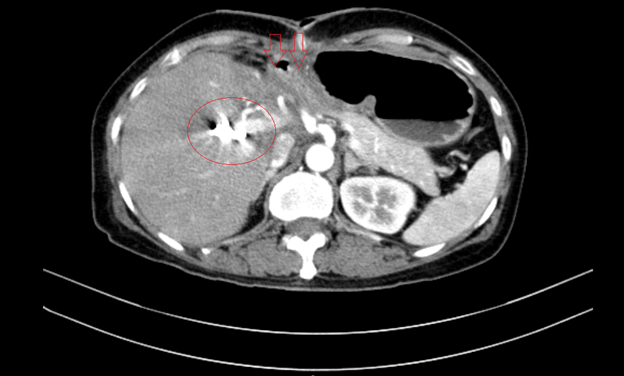

Chụp cắt lớp vi tính bụng – tiểu khung: Hình ảnh giãn đường mật trong gan phải/ Sonde dẫn lưu đường mật gan phải- Gan trái đã cắt.

Hình 7. Phim chụp cắt lớp vi tính vụng cho thấy phần gan trái đã cắt (hình mũi tên)- Sonde dẫn lưu đường mật gan phải( vòng tròn đỏ).

Hình 1. Hình ảnh sỏi đường mật tạo ổ áp xe gan – đường mật gan trái( vòng tròn màu đỏ). Giãn nhẹ đường mật trong gan hai bên. Dày thành nhẹ ngã ba đường mật trên phim chụp cắt lớp vi tính.